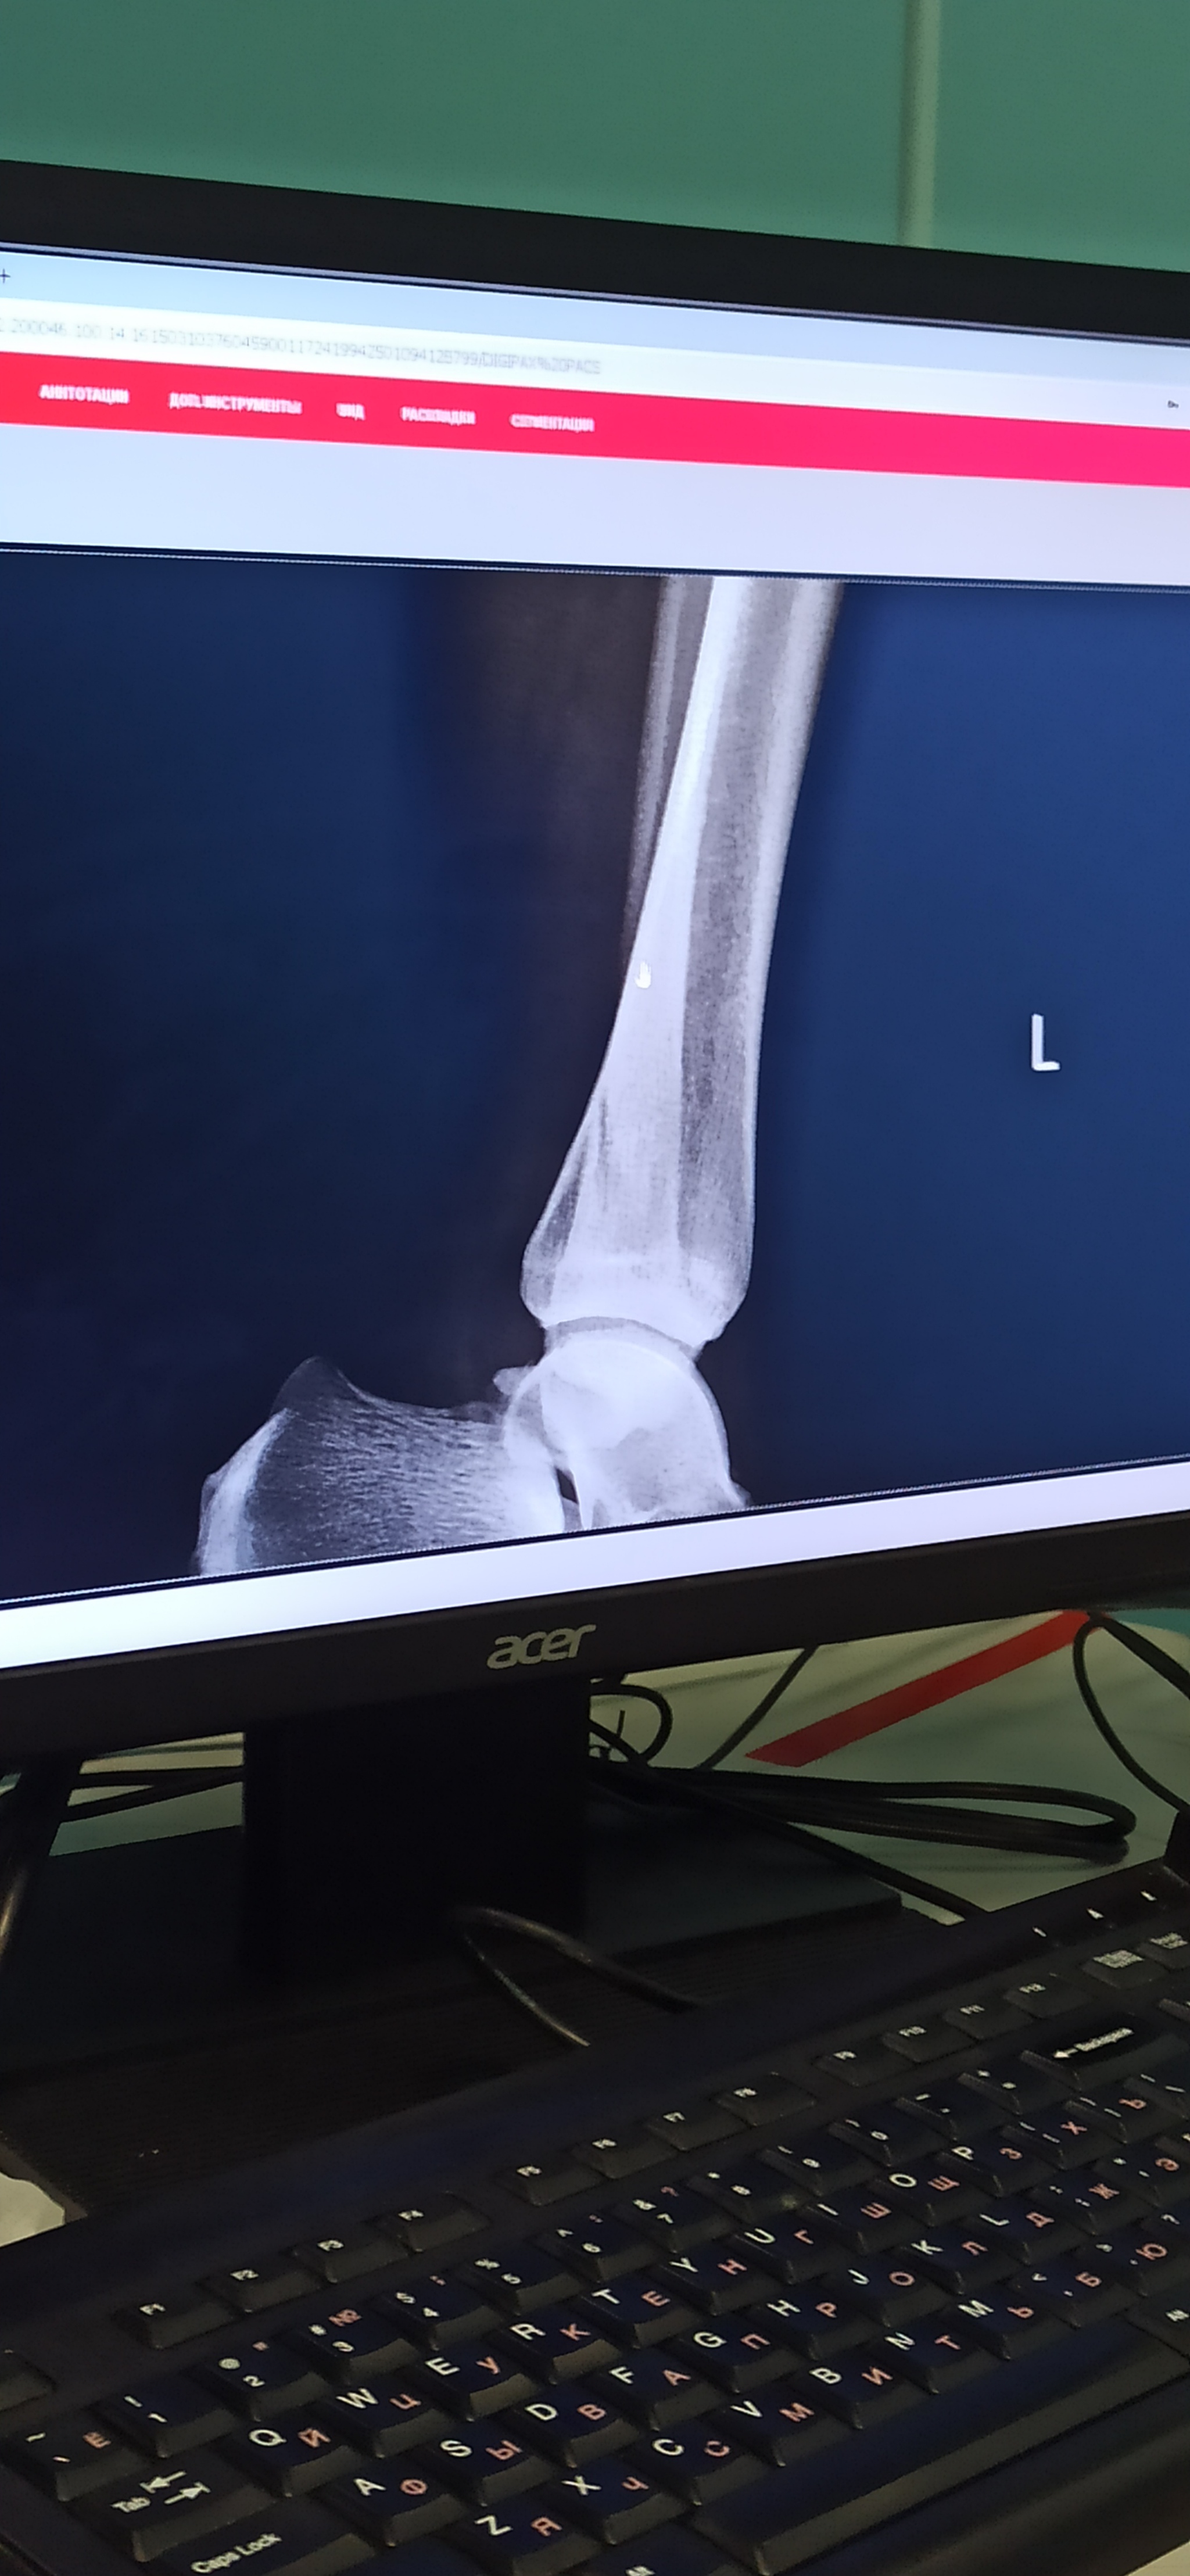

Поскользнулась (очнулась, гипс), закрытый перелом наружной лодыжки.

Пруфы, если надо. Ну мало ли, вдруг кто-нибудь дельного посоветует. И гипс буду менять.